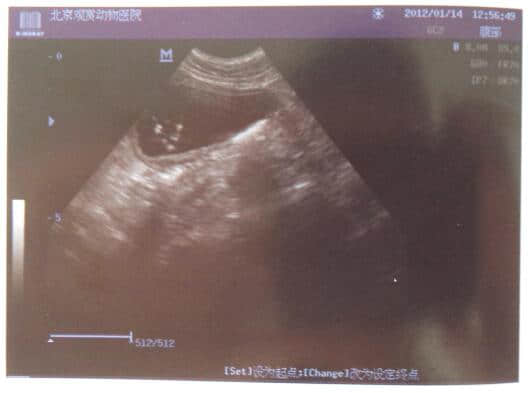

3.2 B超检查如下

从血液化验结果可发现WBC较高达42.62,血清脂肪酶高达4763,而淀粉酶却在正常值,这说明该犬胰腺炎已发病48或72小时以上。并据B超结果和临床症状可诊断为急性胰腺炎、脂肪肝和少量膀胱结石。其以胰腺炎为主。由于血糖较高不排除有糖尿病,建议复查血糖、尿糖。